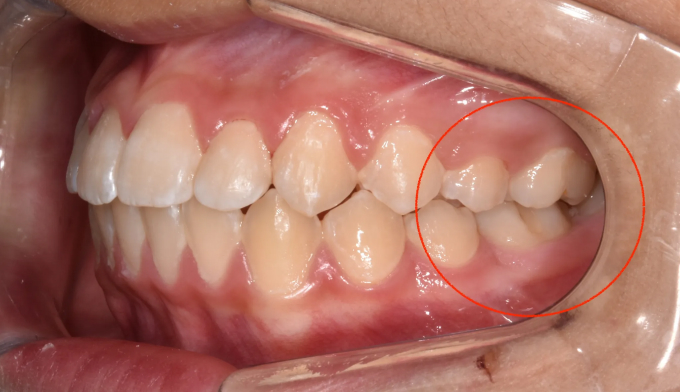

윗니 아랫니가 제대로 물리지 않고 사진에서 표시한 부위처럼 엇갈려서 물리는 경우를 가위교합이라고 합니다.

가위교합은 정상적인 교합이 이루어 지지 못하기 때문에 씹는 효율이 급격히 낮아질 수 밖에 없고, 주변 잇몸조직에도 악영향을 끼칩니다. 심한경우에는 얼굴의 비대칭을 유발하기도 합니다.

나머지 치열들이 양호하다면 굳이 전체교정을 하지 않고 해당부위만 부분교정으로 치료가 가능합니다.

쓰러져있는 치아들을 제위치로 옮겨주면 어렵지 않게 마무리할 수 있습니다.

총 교정기간은 5개월 입니다.